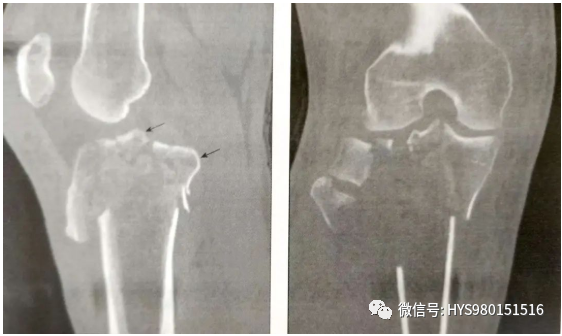

• CT扫描能有效观察关节内骨折情况。标准的扫描应该包括轴位、冠状位和矢状位;

• CT可以提供完整的关节损伤信息,包括髁间嵴骨折,关节面塌陷的位置和程度,骨折块的大小,前交叉韧带撕脱骨折和后交叉韧带胫骨附着点撕脱骨折。

什么是外固定架胫骨近端骨折:环形外固定架_https://www.jmylbn.com_新闻资讯_第6张

▲ 髁间嵴骨折

什么是外固定架胫骨近端骨折:环形外固定架_https://www.jmylbn.com_新闻资讯_第7张

▲ 关节面塌陷的位置和程度

什么是外固定架胫骨近端骨折:环形外固定架_https://www.jmylbn.com_新闻资讯_第8张

A:前交叉韧带撕脱骨折(箭头)

B:后交叉韧带胫骨附着点撕脱骨折

• 它们帮助确定骨折的切口。如一个前外侧髁间嵴骨折,需要采用膝关节外侧入路。

什么是外固定架胫骨近端骨折:环形外固定架_https://www.jmylbn.com_新闻资讯_第9张

▲ 前外侧髁间嵴骨折(箭头)